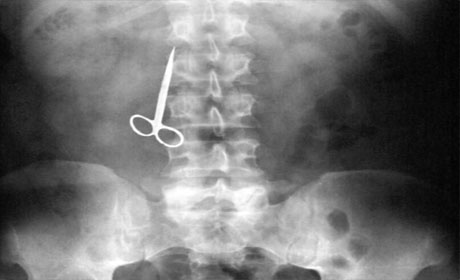

Mədəsindən əl bombası çıxdı - ŞOK FOTOLAR

İnsan nələri udmağa qadir deyil? Yaxud mədədən nələr gəlib-keçmir? ANN.Az-in oxuculara təqdim etdiyi fotolar bir daha insanın nələrə qadir olduğunu göstərir. 1. İlan balığı2. Qaşıq3. Batareyalar4. Canlı qurbağa5. Mismar6. Dərmanlar 7. Nişan üzüyü8. Qayçı9. Tük yumağı10. Mobil telefom11. Qələm12. Yay13. Əl bombası14. Açar15. Lampa